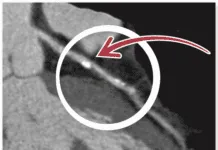

If you have ever felt your heart racing or jumping, you have experienced the symptoms of atrial fibrillation (afib). Its a distressing-even frightening-sensation that usually resolves in a few seconds. But if it lasts more than several days or returns from time to time, it can increase your risk of stroke five-fold.